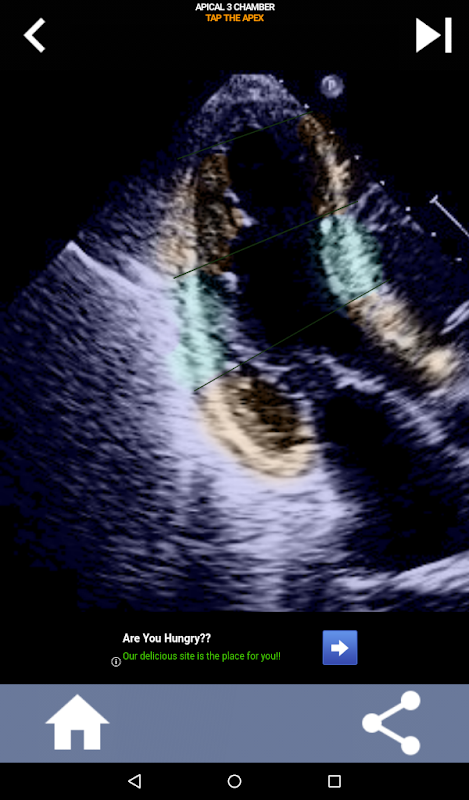

Enfoque visual basado en cuestionarios para aprender los segmentos cardíacos de la AHA: ecocardiografía

Esta aplicación pondrá a prueba su conocimiento utilizando imágenes de eco reales, que a menudo encuentro que es el mejor método de enseñanza.